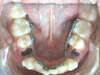

Vues avant le traitement